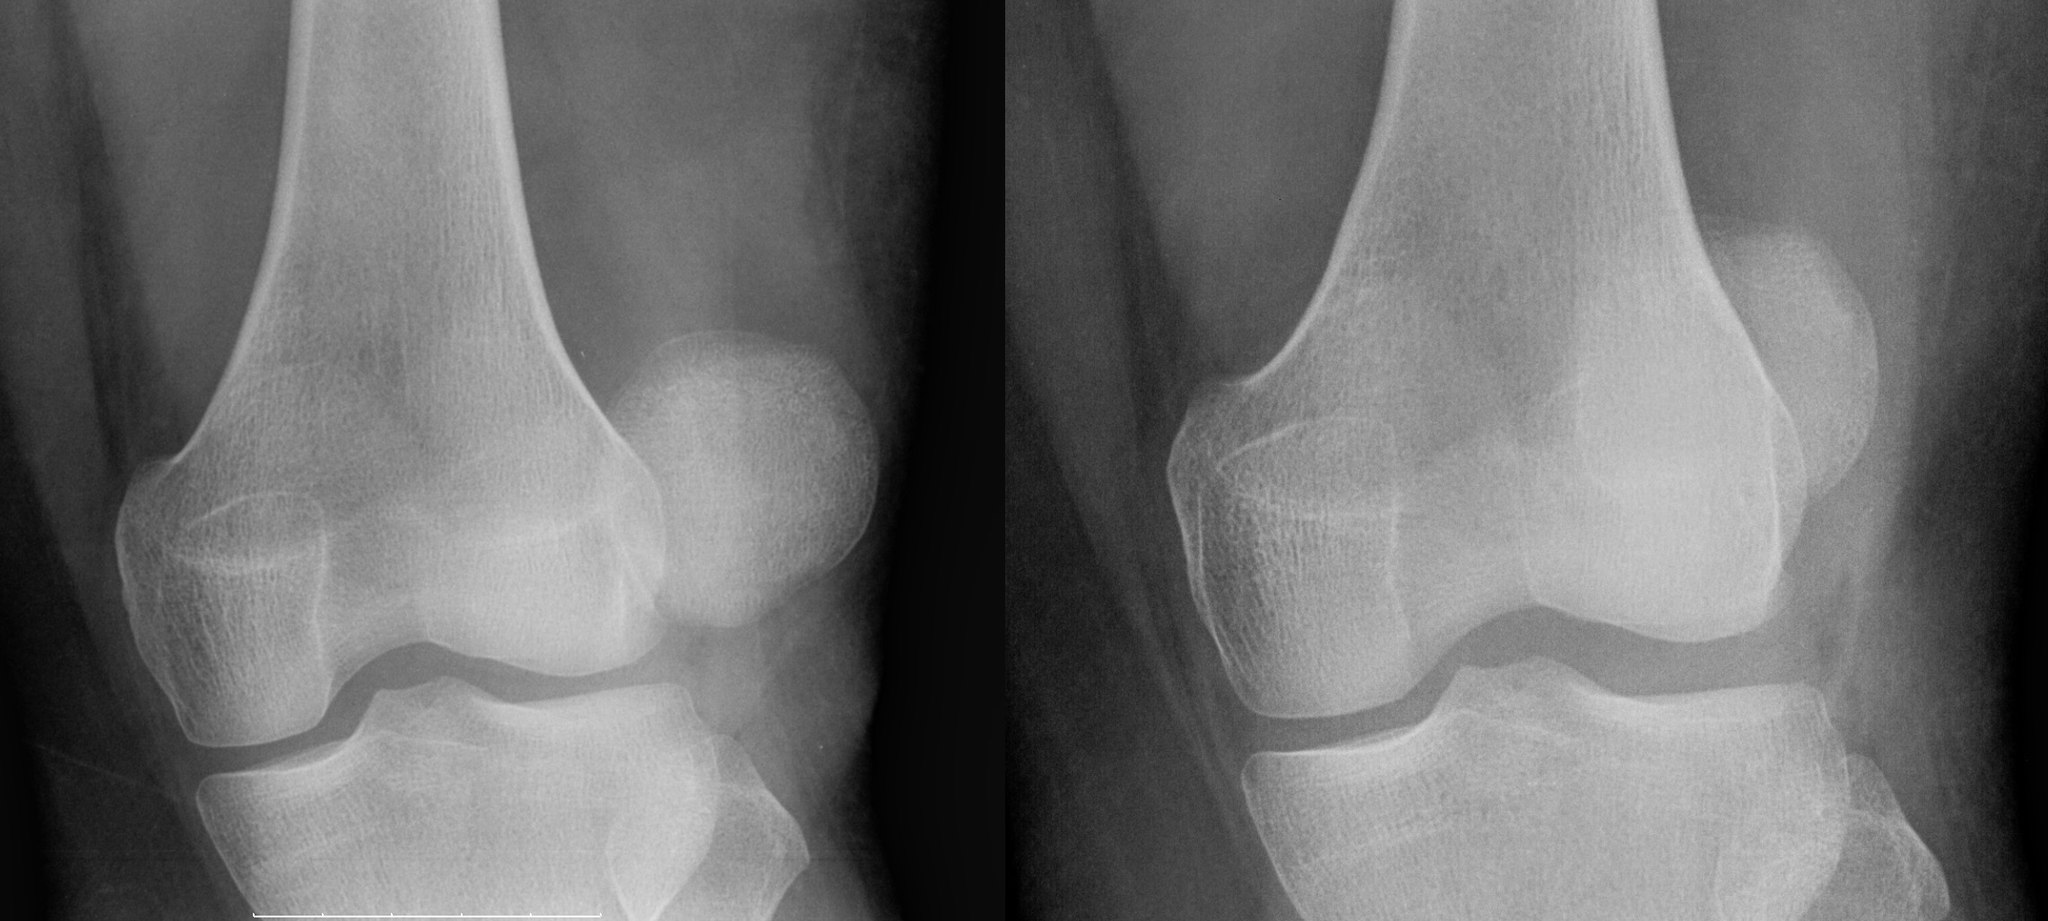

Luxating Patella Correction

Commonly known as the “knee cap”, the patella can become dislocated. Drifting out of place, it tends to cause your animal to hold their leg in the flexing position. The slipped patella causing the knee to lock and hold. This can happen in both cats and dogs, often manifesting in smaller breeds. Severity and affect are variable. Grade 1-2 may include holding up the leg a few steps, or skipping to a more severe condition which may lead to being unable to extend the leg, bowing or a pigeon-toed posture.

There are surgical correction options available at TLC Pet Hospital. The surgery is designed to improve leg function and to resist degenerative joint disease with the stabilization of the patella in the trochlea. The surgery is a good option for older pets who have lost mobility. 95% of dogs undergoing the repair will produce significant improvement in knee function.